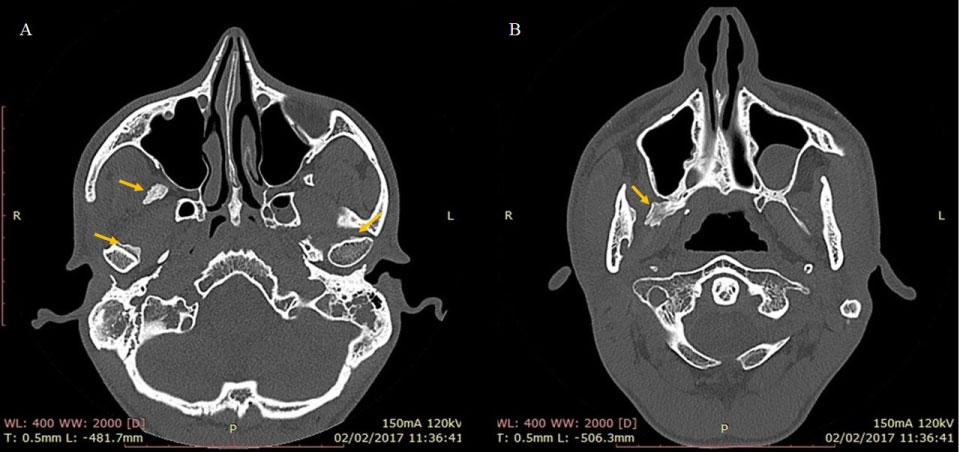

Magnetic Nuclear Resonance (MRI) examination of TMJ revealed articular discs with normal signal intensity and morphology only in the closed mouth, since the other positions were not possible due to severe trismus. An inflammatory process with thickening of the medial and lateral pterygoid muscles on the right was also observed, with no collections. CT examination revealed the presence of bilateral calcification in the medial and lateral pterygoid muscles, and the right medial pterygoid muscle presented greater involvement by the pathology (Figure 3 and Figure 4). The results found in the imaging examinations, along with the clinical examination, suggested the diagnostic hypothesis of MOT of masticatory muscles.

Figure 3: Preoperative CT axial plane, with seven months after dental extraction. Location of the lesion marked by the yellow arrow. View Figure 3

Figure 4: Coronal plane of preoperative CT, with seven months after dental extraction. Location of the lesion marked by the yellow arrow. View Figure 4